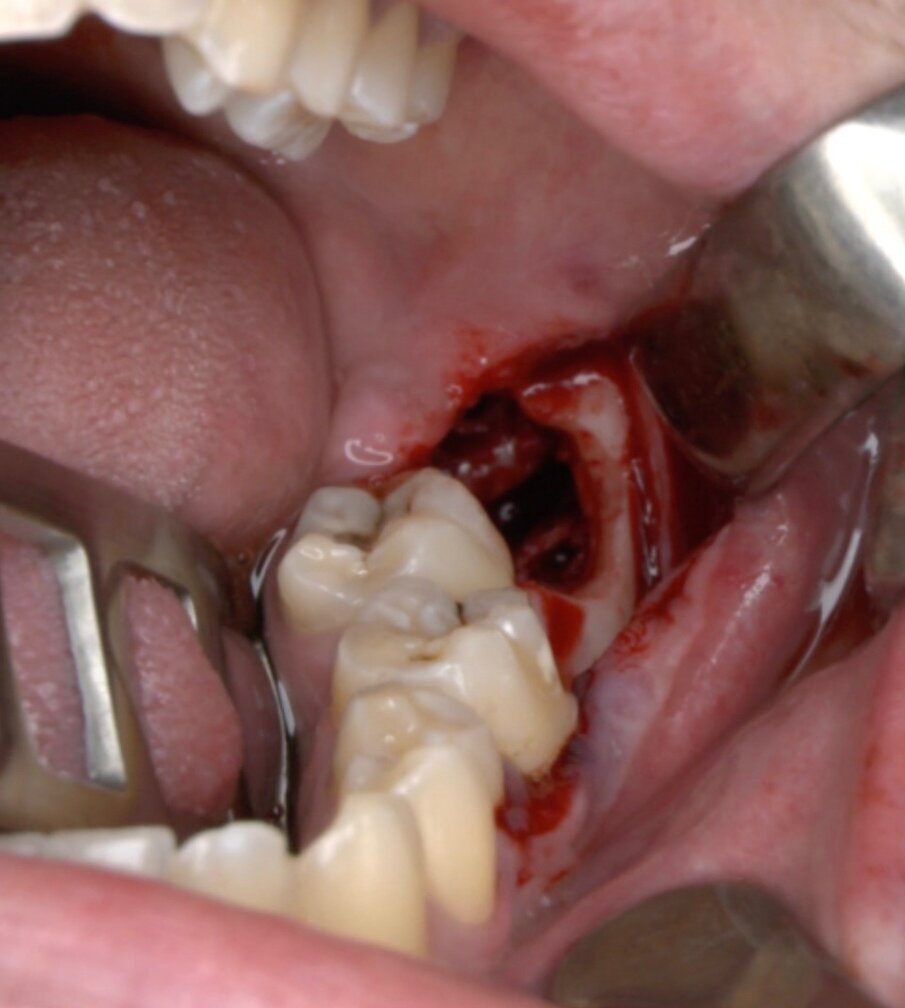

Ai pazienti viene prescritta una profilassi antibiotca con 2 gr di amoxicillina 1 h prima dell’intervento, si esegue quindi un anestesia di tipo tronculare con lidocaina senza vasocostrittore, poi infiltrazione di tipo plessica con adrenalina in corrispondenza del nervo buccinatore. Si scolpisce quindi un lembo a tutto spessore di tipo triangolare con incisione orizzontale alla base delle papille tra sesto e settimo ed incisione di scarico distale con andamento vestibolare (Figg. 1-4). Si procede con l’osteotomia che può essere eseguita con strumenti rotanti montati su manipolo retto oppure con terminale piezoelettrico con gli inserti dedicati. Qualora sia necessario si effettua l’odontotomia e la separazione radicolare con frese al carburo di tungsteno montate su turbina, quindi si esegue la lussazione e l’avulsione dell’elemento dentario. Si procede alla revisione della cavità alveolare con abbondante lavaggio con soluzione fisiologica, riempimento con collagene e sutura a punti staccati in seta 4/0. Il paziente viene dimesso con terapia analgesica ed antibiotica di supporto (Figg. 5-15).

Fig. 5_Ostectomia con terminale piezoelettrico.

Fig. 6_Terminale piezoelettrico in azione.

Fig. 7_Ostectomia completata.